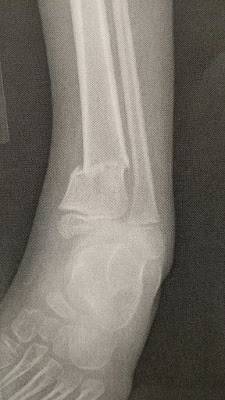

Our sweet boy just can't catch a break (haha). While playing on the trampoline 10 days ago, he broke his leg, both bones at the ankle. I knew immediately it was broken, he was shaking head-to-toe just like he was when he broke his arm. We quickly realized we had to call 911, as we had no way to keep it stabilized in our van to get him to the hospital. He was in so much pain, it was awful. It was traumatic for all of us. He was in pain, the other kids were scared and I lost any semblance of "calm and cool" mom.

Casting was super stressful for this guy. Thankfully, after much discussion, they agreed to put the cast on below the knee instead of above the knee as they typically do. If it was above the knee, then we'd continue to struggle to get him in the van and he also couldn't ride the school bus in the rental wheelchair, so we were going to be in a transportation bind. I'm so thankful that it's below the knee= we can use his custom chair for the bus and he can get his leg in the van easier. We just have to be very careful that he doesn't bear any weight on that leg at all, which means he relies on us for his every move.

The ortho doc wants to keep close tabs on the breaks to make sure they're healing properly, so we go back in a few days for new x-rays to see how it's doing. We're very hopeful that they won't have to "manipulate" the bones to help them heal properly as they indicated could be a possibility. This poor kid has been through so much medical trauma, we need his healing to go as smoothly as possible.